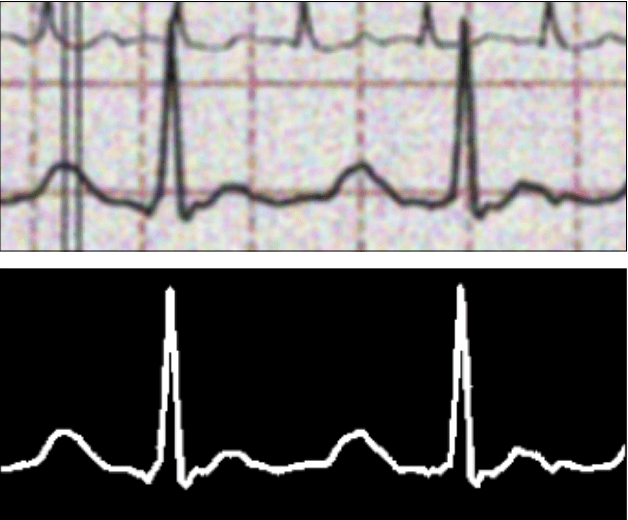

Abstract:This paper addresses the persistent challenge of accurately digitizing paper-based electrocardiogram (ECG) recordings, with a particular focus on robustly handling single leads compromised by signal overlaps-a common yet under-addressed issue in existing methodologies. We propose a two-stage pipeline designed to overcome this limitation. The first stage employs a U-Net based segmentation network, trained on a dataset enriched with overlapping signals and fortified with custom data augmentations, to accurately isolate the primary ECG trace. The subsequent stage converts this refined binary mask into a time-series signal using established digitization techniques, enhanced by an adaptive grid detection module for improved versatility across different ECG formats and scales. Our experimental results demonstrate the efficacy of our approach. The U-Net architecture achieves an IoU of 0.87 for the fine-grained segmentation task. Crucially, our proposed digitization method yields superior performance compared to a well-established baseline technique across both non-overlapping and challenging overlapping ECG samples. For non-overlapping signals, our method achieved a Mean Squared Error (MSE) of 0.0010 and a Pearson Correlation Coefficient (rho) of 0.9644, compared to 0.0015 and 0.9366, respectively, for the baseline. On samples with signal overlap, our method achieved an MSE of 0.0029 and a rho of 0.9641, significantly improving upon the baseline's 0.0178 and 0.8676. This work demonstrates an effective strategy to significantly enhance digitization accuracy, especially in the presence of signal overlaps, thereby laying a strong foundation for the reliable conversion of analog ECG records into analyzable digital data for contemporary research and clinical applications. The implementation is publicly available at this GitHub repository: https://github.com/masoudrahimi39/ECG-code.